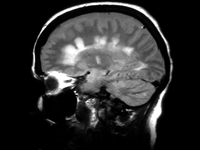

过去30年间,脑结构和功能影像学得到迅速发展,大大提高了评估基底节功能、诊断帕金森综合征、理解帕金森病(PD)及其他运动障碍疾病的病理生理、检测和监测疾病进展的能力。现将本次AAN会议中关于PD功能影像学研究作一阐述。